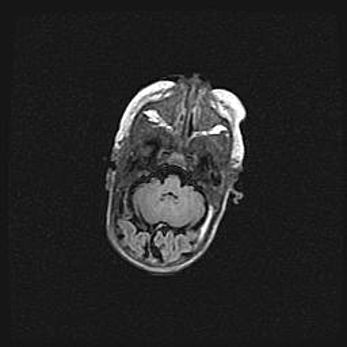

Множественные кисты обоих полушарий головного мозга, наибольшая из них в правой затылочной области. Ассиметричная атрофическая гидроцефалия.

Возраст: 7 месяцев

Вес: 5660 г

Пол: мужской

Окружность головы: 41,5 см

Срок гестации: 28-29 недель

Кисты головного мозга развиваются в результате многоочаговых некрозов вещества мозга и возникают вследствие перенесенной перинатальной инфекции, менингитов, энцефалитов, асфиксии, родовой травмы, расстройств мозгового кровообращения различного генеза. Образованию кист в веществе головного мозга плодов и новорожденных способствуют такие факторы, как высокое содержание в нем воды, недостаточная (или отсутствие) миелинизация и слабая астроглиальная реакция на повреждение.

Кисты могут сочетаться с гидроцефалией и другими поражениями головного мозга.